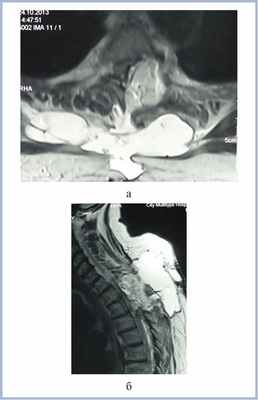

На 20-е сутки после первой операции выполнено очередное (3-е) оперативное вмешательство: наложение дополнительных герметизирующих швов на фасциальную заплату ТМО, удаление из эпидурального пространства жирового лоскута, герметизация ТМО мышечным лоскутом на ножке. В послеоперационном периоде отмечено увеличение силы в ногах до 4 баллов. В удовлетворительном состоянии выписана из стационара при сохраняющихся явлениях заднестолбовой атаксии, оценка по шкале Klekamp—Samii — 18 баллов.

При контрольном осмотре через 5 мес после удаления опухоли несколько улучшилась чувствительность в ногах, ходит с опорой на костыли, оценка по шкале Klekamp—Samii — 19 баллов. Контрольная МРТ пациентки через 5 мес после операции представлена на рис. 4.

Рис. 4. МР-томограммы (Т2-ВИ) пациентки с менингиомой на уровне Th3—Th4 позвонков в аксиальной (а) и сагиттальной (б) проекциях через 5 мес после операции. Определяется небольшая ликворная киста без компрессии спинного мозга.